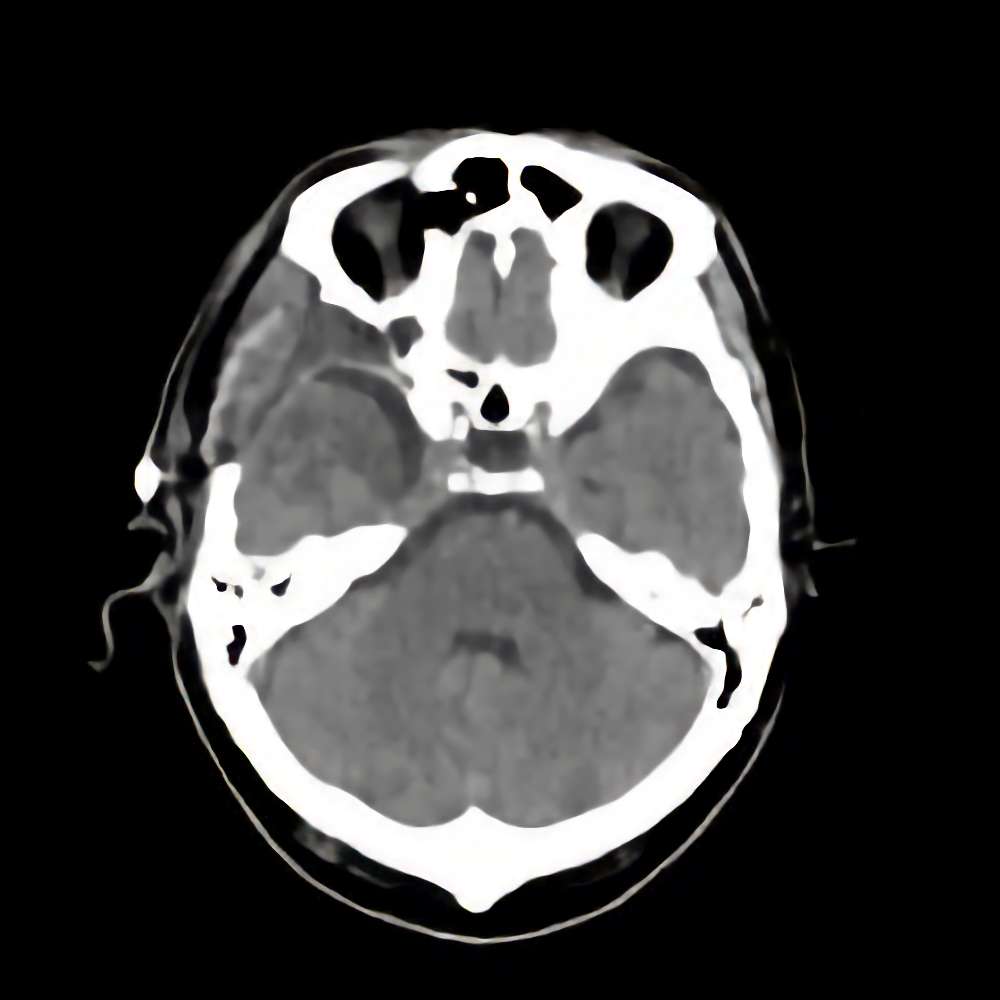

蝶形骨稜髄膜腫

断層撮影

手術前1

No.’14_142 手術前1

No.’14_142 手術後